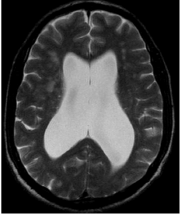

Homem de 70 anos relata quadro de alteração de marcha com base alargada, lentificação e quedas que se iniciou nos últimos 4 meses, seguido de apatia, irritabilidade, déficit de memória, confusão mental, desorientação. Nas últimas semanas vem apresentando urgência urinária. É solicitado exame de imagem, a seguir.

Enunciado 3507707-1

A hipótese diagnóstica é